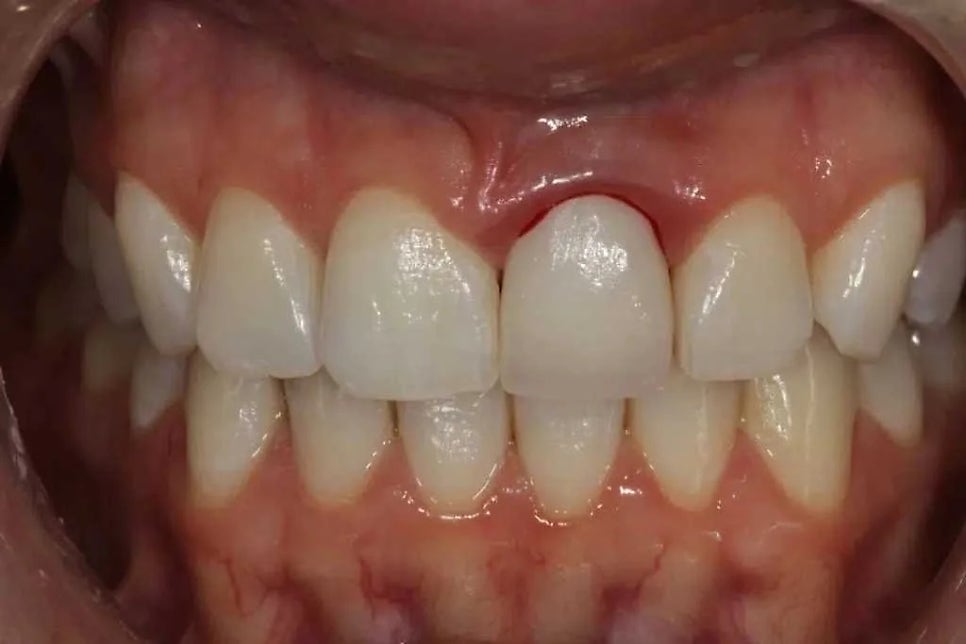

심한 경우 잇몸이 붓는걸 넘어 피까지도 나는 경우가 있습니다. 크라운 문제인지, 잇몸의 문제인지 궁금하시죠? 거기만 그런지 다른 일반 치아들도 그런지 비교해보시면 됩니다. 당연한 말이지만 만약 크라운 주위만 그렇다면, 그건 크라운의 문제일 가능성이 큽니다. (출처: https://www.drscottfroum.com/)